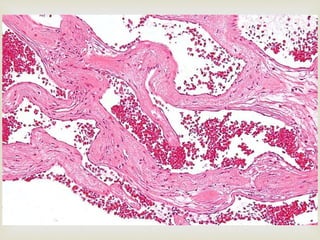

 Cavernous hemangioma

 Large dilated blood sinuses with thin walls showing

endothelial cells

 Sinusoidal spaces are usually filled with blood

 Sometimes lymph vessels may be present

HEMANGIOMA